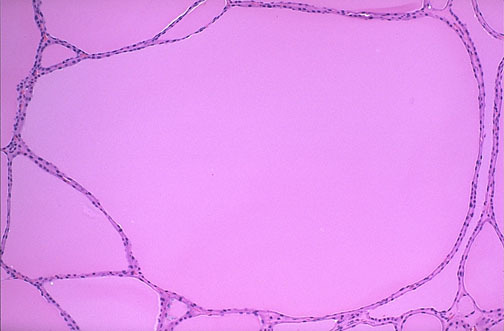

Normal thyroid seen microscopically consists of follicles lined by a cuboidal epithelium and filled with pink, homogenous colloid. The follicles vary somewhat in size. The interstitium, which may contain “C” cells, is not prominent.